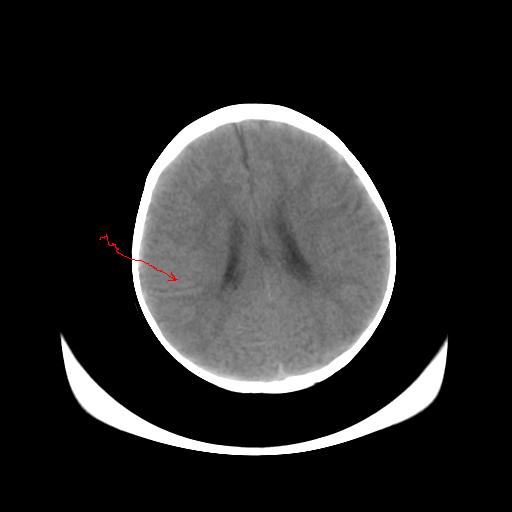

女,10个月,头外伤三天,伤后爱哭闹,吃奶少,睡觉不踏实。

左侧颞极蛛网膜囊肿

1)左侧颞极蛛网膜囊肿。2)第四脑室出血?

1、左侧颞极蛛网膜囊肿;2、第四脑室出血?3、右侧顶叶脑裂畸形伴灰质异位?

1)左侧颞极蛛网膜囊肿。2)第四脑室内高密度影,性质待定。